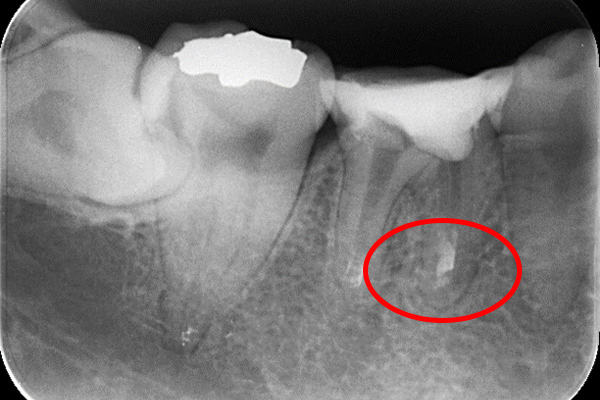

①自覚症状なし・歯肉にサイナストラクト(排膿路)あり

②初診時レントゲン解説

・歯根周囲に透過像(黒い影)あり

・遠心根根管充填:アンダー

根管治療そのものは、2回で終了し、水酸化カルシウム貼薬し経過観察(患者様希望のため)

約2か月後、根尖透過像の縮小を確認し根管充填(MTA使用)。

レントゲン解説:4根管すべてに根管充填が密にされていることを確認できる

透過像は消失し、明らかな骨形成を認める。(黒い影の消失)